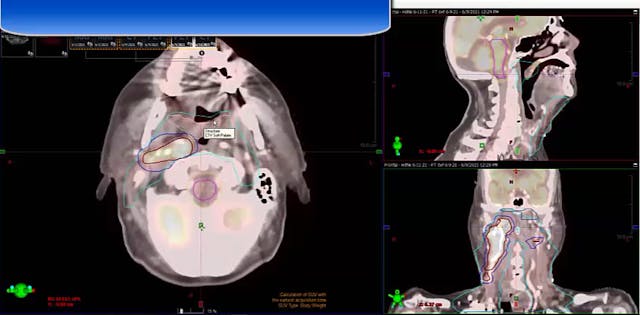

12/14/18 - Dr. Kenneth Hu - Radiation Oncology - Head and Neck US

Chartrounds US - Head and Neck Cancer

Neck mass carcinoma, unknown primary, tonsillectomy, neck dissection and rapid lymph node regrowth, dose, treatment fields, de-escalation for HPV